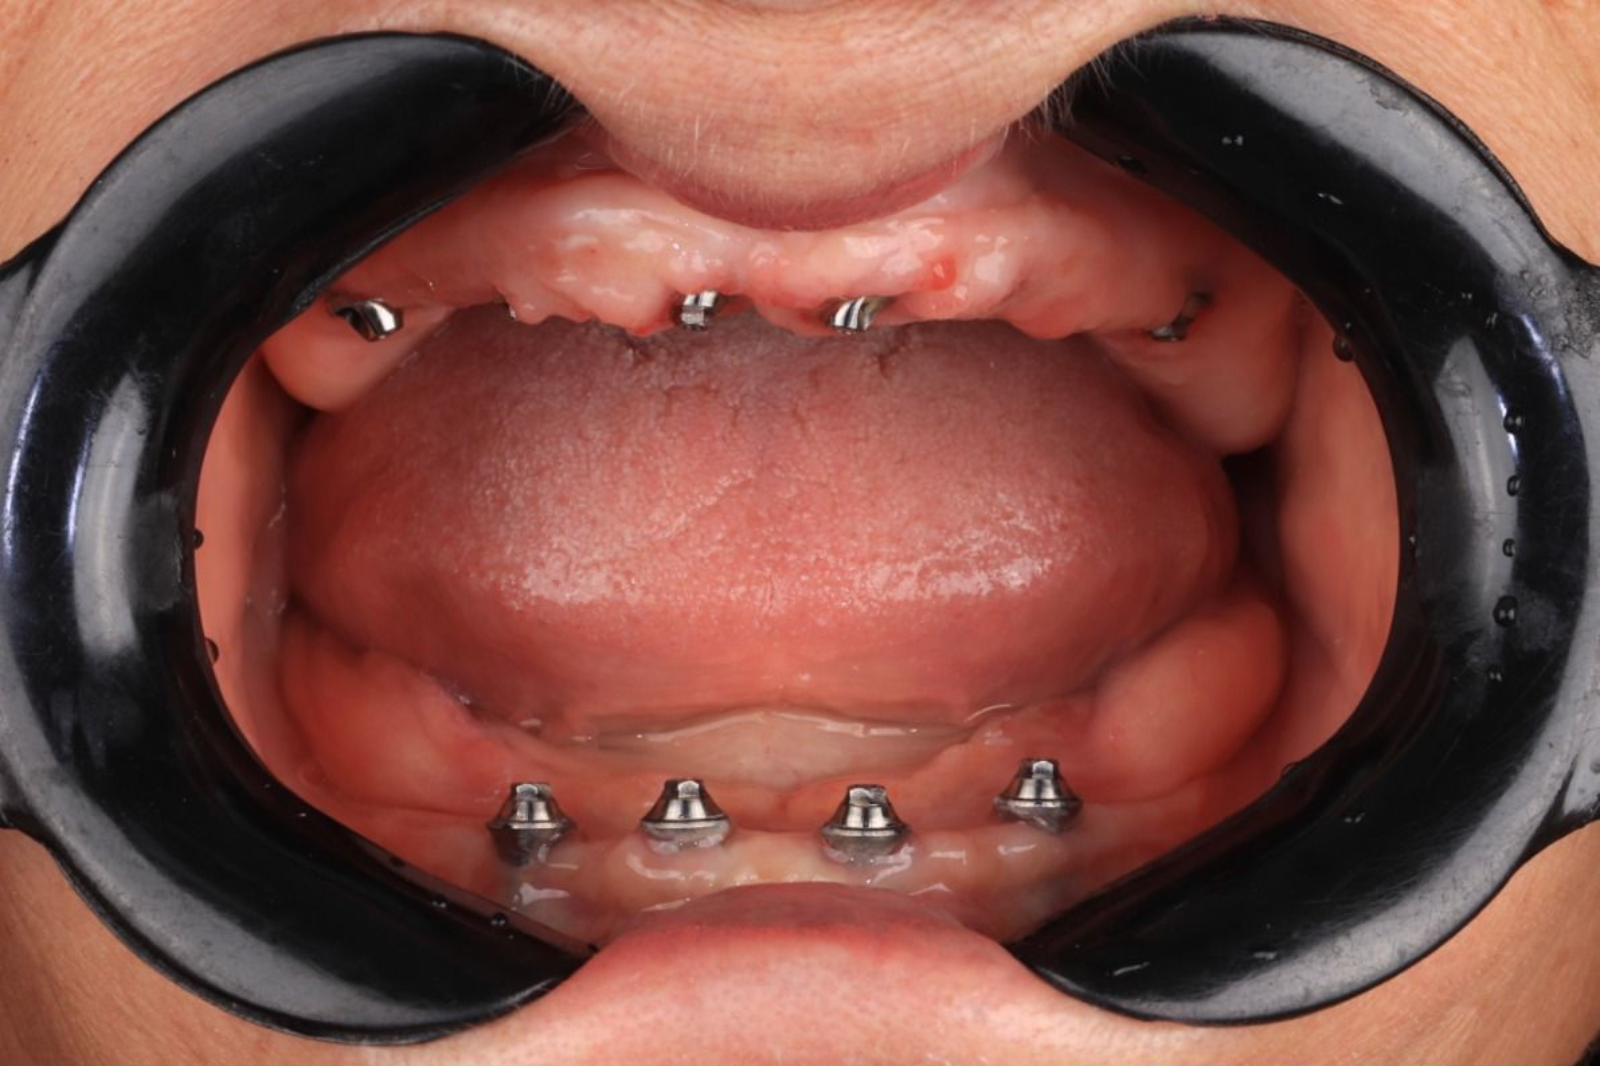

Antes & depois — arraste para comparar

Casos reais tratados na clínica. Deslize o divisor para ver a transformação.

Resultados da clínica